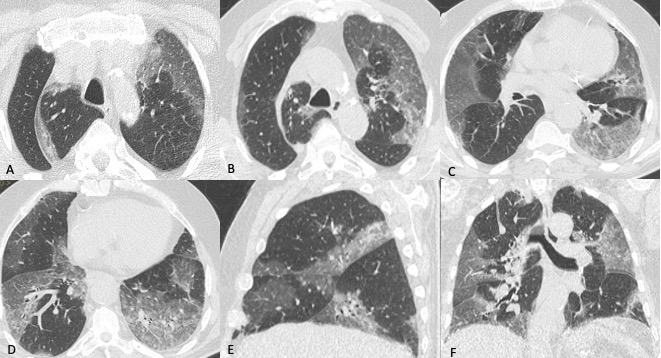

In TCAR la polmonite batterica si manifesta con aree di aumentata densità con aspetto prevalentemente consolidativo ed in parte a “vetro smerigliato” con broncogramma aereo nel contesto e che mostrano distribuzione lobare o segmentaria senza predilezione dei lobi inferiori (Figura 6).

Figura 6: Donna di 73 anni giunge in Pronto Soccorso per febbre, dispnea e dolore addominale. La TCAR eseguita due giorni dopo il ricovero (immagini assiali A-B-C e ricostruzione MPR sul piano coronale D), mostra la presenza nel lobo superiore sinistro di un’area di aumentata densità con aspetto prevalentemente consolidativo ed in parte a "vetro smerigliato" con broncogramma aereo nel contesto, reperti tipici di polmonite batterica. Il BAL eseguito in seguito conferma l’ipotesi di polmonite batterica, l’agente eziologico isolato è la Legionella.

Figura 7: Uomo di 67 anni ricoverato per polmonite batterica confermata anche dalla radiografia del torace eseguita all’ingresso in Pronto Soccorso. In considerazione dell’aggravarsi del quadro clinico viene richiesto un approfondimento diagnostico tramite TCAR (immagini assiali A-B ed MPR coronale C ed MPR sagittale D), da cui si evidenzia la presenza nel lobo inferiore dx di un area di aumentata densità con aspetto consolidativo nel cui contesto si osservano multiple aree a densità aerea, reperti compatibili con ascesso polmonare, possibile complicazione della polmonite batterica.